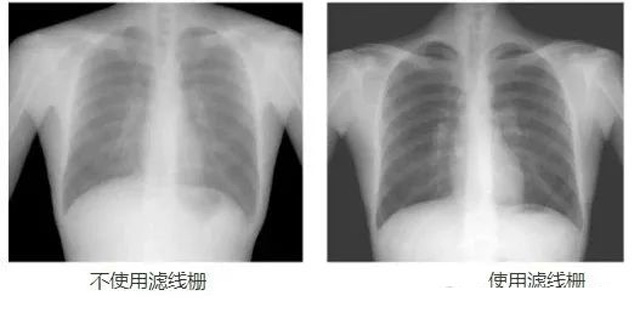

DR影像X射線在醫(yī)學(xué)檢查成像有著廣泛的使用。但是它的散射線影響成像質(zhì)量問題。濾線柵的發(fā)明使用很好的解決了這個問題,構(gòu)造簡單鉛條粗,密度和柵比規(guī)格單一,能減散射線但吸收較多原發(fā)射線。伴隨這醫(yī)療影像設(shè)備技術(shù)的發(fā)展,這個濾線柵的工藝制造技術(shù)有改進(jìn),鉛條變薄,柵密度和柵比有更多的選擇。特別是材料方面有新組合,填充物也依不同成像要求優(yōu)化。特別是移動DR這類型的DR設(shè)備的出現(xiàn),濾線柵也設(shè)計成立方便拆卸形的,方便使用。被照體情況決定是否使用,更好平衡成像質(zhì)量與射線劑量。